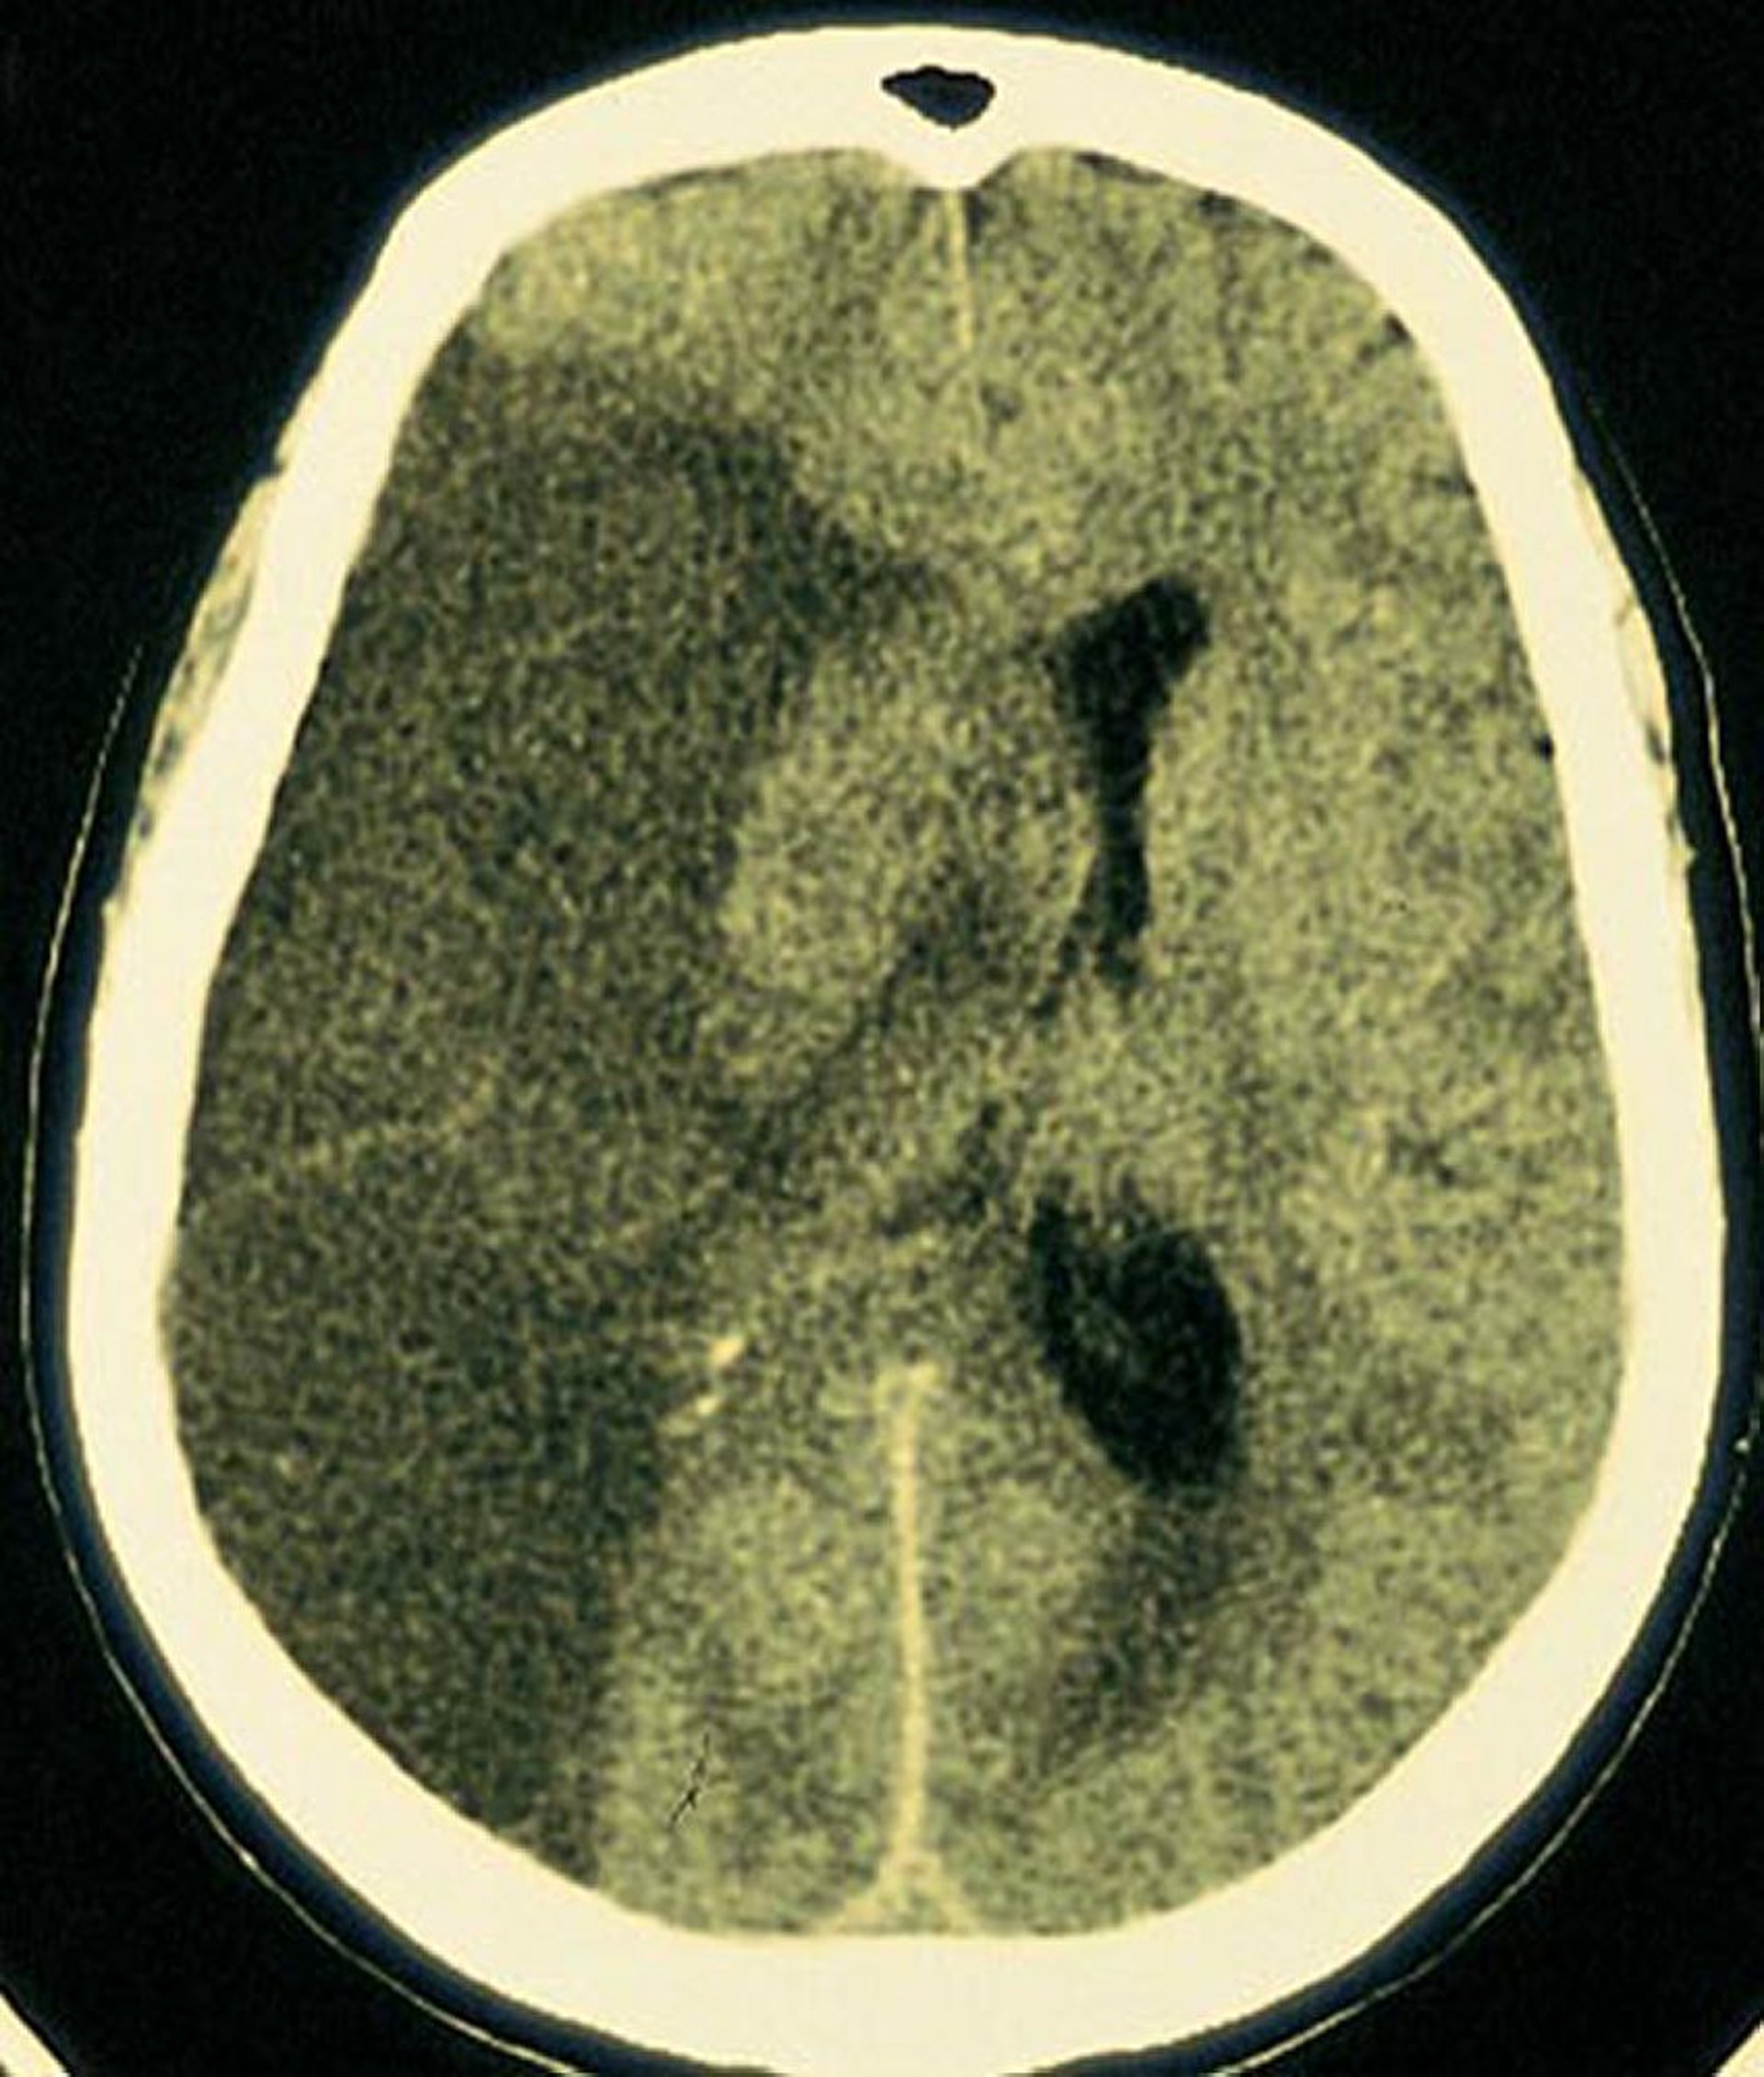

Infarto de la arteria cerebral media

Se observa un gran infarto radiolúcido en el área del encéfalo irrigada por la arteria cerebral media derecha.